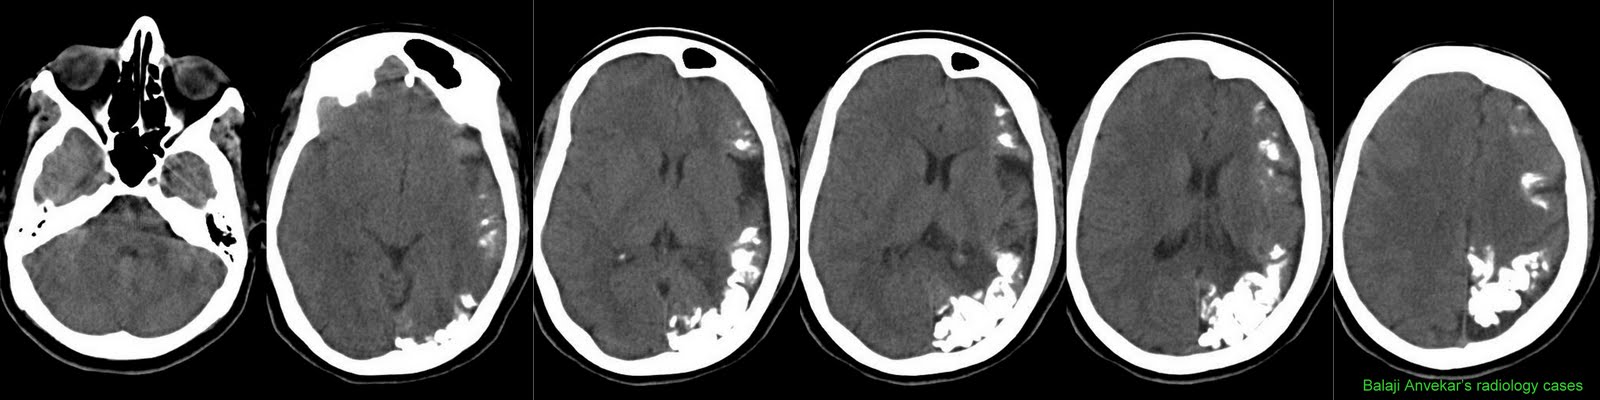

Home » Tram Track Sturge Weber Syndrome Radiology » Tram Track Sturge Weber Syndrome Radiology

Tram Track Sturge Weber Syndrome Radiology